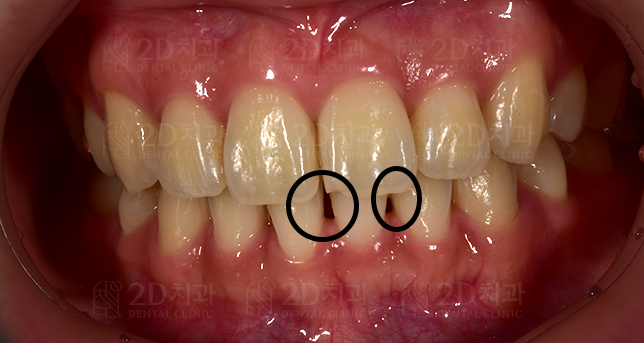

<사진> 블랙트라이앵글

사진에 표시된 부분을 블랙트라이앵글이라고 합니다.

이 블랙 트라이앵글의 크기가 크면

김처럼 까만 무언가가 치아사이에 끼인걸로 보일 수도 있겠죠? ^^

< 사례 1 >

블랙트라이앵글 무삭제라미네이트 <블랙필름> 치료 전